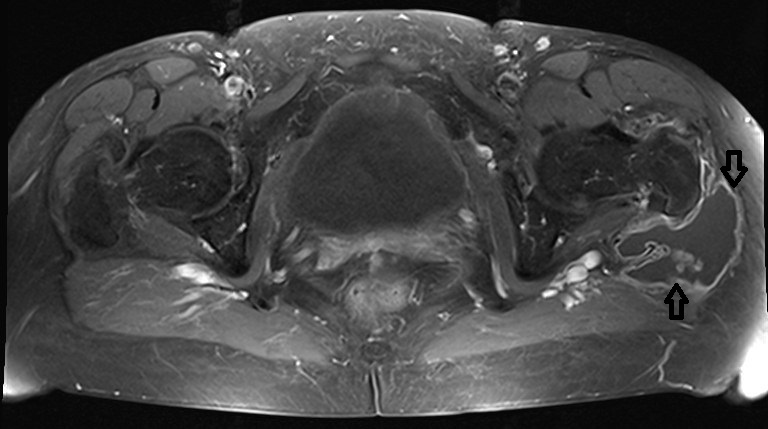

Lateral to the greater trochanter in the bursa trochanterica there was evidence of fluid showing homogeneous hyperintensity without sedimentation in fluid-sensitive sequences. Proton-weighted imaging revealed two nodular wall extensions in teardrop shape extending craniolaterally. These extensions measured a maximum of 1 cm at the base. In addition, at the roof of the fluid-filled cavity there was a space measuring approximately 1.5 x 0.5 cm. In the native fat-suppressed T1 turbospinecho sequence, this space-occupying lesion was partially hyperintense. This was considered to be hemosiderin. After application of gadolinium, there was a vigorous enhancement of the lining of the height. In addition, there was diffuse enhancement of the muscles in the immediate vicinity of the bursa. The hemorrhaged mass showed no enhancement of the contrast medium. In summary, the recent MRI exhibited an enlarged trochanteric bursitis with some intrabursal soft tissue formation suspicious for pigmented villo-nodular synovitis (PVNS) of the bursa trochanteric (PVNSBT) (Figure 1 [Fig. 1], Figure 2 [Fig. 2], Figure 3 [Fig. 3], Figure 4 [Fig. 4]).

Figure 2: Proton-weighted transversal plane exhibiting the enlargd bursa filled with fluid and soft-tissue protruded into the bursa trochanterica (marked by an arrow)

Figure 3: T-1 weighted fat-suppressed transversal plane with contrast medium exhibiting the enlargd bursa filled with fluid and soft-tissue protruded into the bursa trochanterica and surrounded by contrast medium (marked by the arrows)